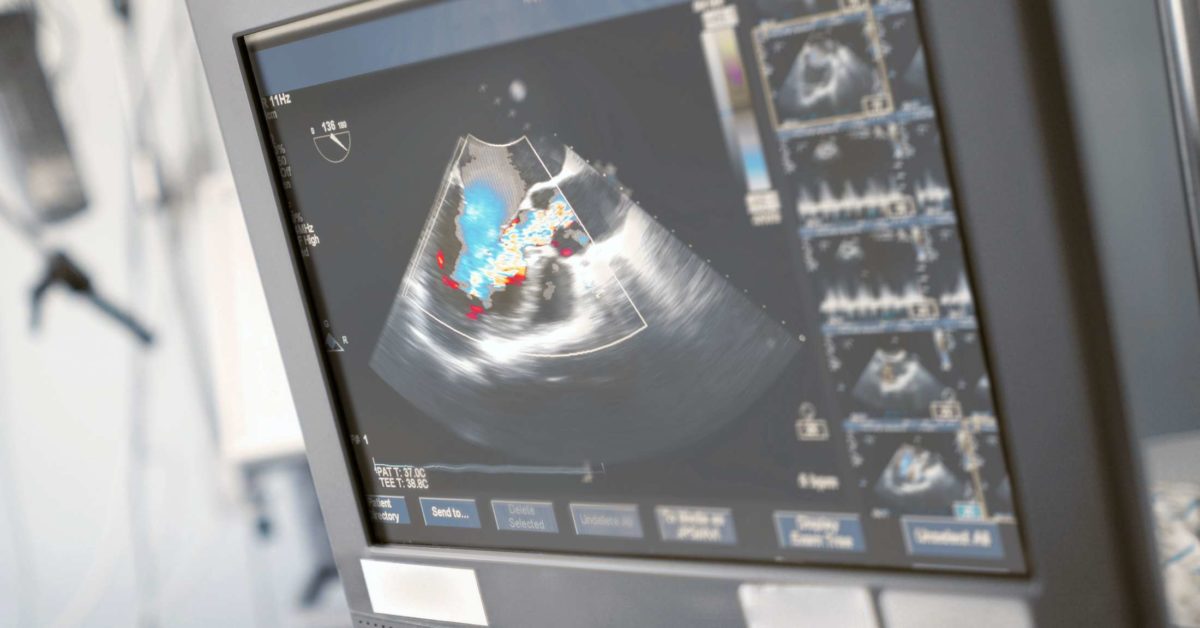

What is the most common type of echocardiogram?

There are different types of echocardiograms, which include: The transthoracic echocardiogram (TTE), which is the most common device. By moving the transducer along your chest wall or abdominal wall, different views of the heart can be obtained.

The high-pitched sound waves are sent through a transducer and the device picks up the echoes as they bounce off the tissue of your heart. The echoes are converted into moving images of the heart, which can be viewed on a video screen. There are different types of echocardiograms, which include:

This allows clearer pictures of your heart to be shown, since the probe has a closer proximity to the heart and the lungs and tissues in the chest wall do not obstruct sound waves from the probe. A local anesthetic in the throat and a sedative may be used to keep you comfortable during the test.